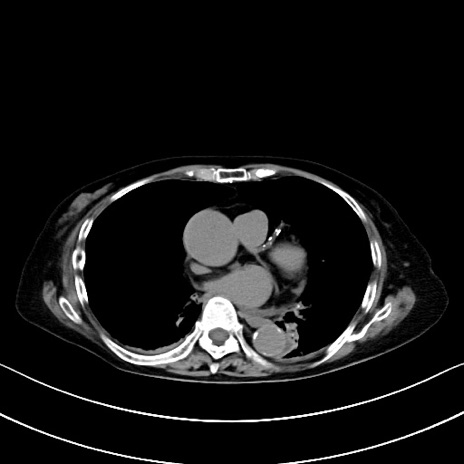

横断像

冠状断像